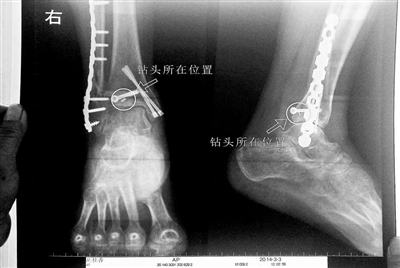

胡女士的腿部X光圖

看著X光片中自己腿內的異物,胡女士就感到莫名的擔憂。胡女士于2013年3月在北京市豐臺區右安門醫院進行了一次骨折手術,術后醫生才發現手術時用來打眼用的鉆頭不慎遺留在了胡女士的骨頭中,并且無法取出。

近日,在豐臺區右安門醫院,北京青年報記者見到了胡女士,她走起路來顯得一瘸一拐,腿腳并不利索。在她帶來的X光片上,可以清晰地看到,有一個異物存在于腿內部。

“我當時就嚇蒙了,怎么會有一個鉆頭在骨頭里?”胡女士余悸未消地說,第二天拍攝的X光片顯示,2厘米左右的鉆頭遺留在她右腳腳踝上部的骨頭內。

胡女士說,當時旁邊的醫生勸慰自己,稱鉆頭留在腿里并不會有什么問題。出院后,胡女士每個月都會來醫院做復查,拍X光片。她說,每次都能夠清晰地看見自己骨頭里的那個明晃晃的“小東西”。

“留在她腿里的鉆頭確實無法取出。”徐主任解釋說,按常理說,鉆頭不應該斷在里面,但現在事情確實發生了。鉆頭沒有折在關節,而是在跖骨內,跖骨主要起支撐作用,不像關節那樣起活動作用,而且這個部位比較質密,并非像肌肉要經常活動受到擠壓。